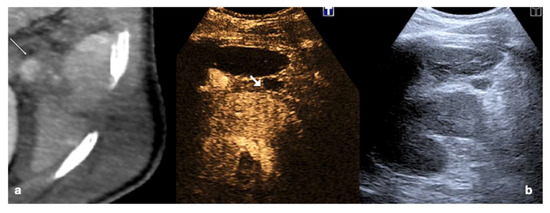

4.3. Step 3

Figure 24.

An example of multimodal visualization of post-traumatic splenic PSA (white arrows) at CD–US (a), CEUS (b), and arterial phase contrast-enhanced CT scan (c); CEUS follow-up examination after embolization (d) showed no evidence of residual PSA.

Figure 25.

Splenic trauma in car accident with small splenic laceration visible on contrast-enhanced CT scan performed at emergency department (a,b, white arrowhead). CEUS examination performed 4 days after trauma confirmed the splenic laceration (c, white arrowhead); subsequent Flash mode CEUS (d) revealed multiple, small and diffuse intra-splenic PSAs (white arrows) not shown at admission arterial phase CT exam (a); these findings were confirmed at contrast enhanced CT scan (e, arrows) and angiography (f, arrows).